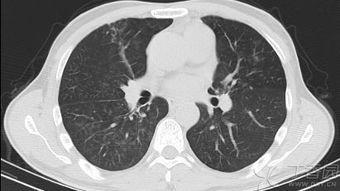

肺玻璃可以帮助医生更准确地诊断肺部疾病,比如肺炎、肺结核、肺癌等。通过观察肺部的透明图像,医生可以清晰地看到病变部位,从而做出更准确的诊断。